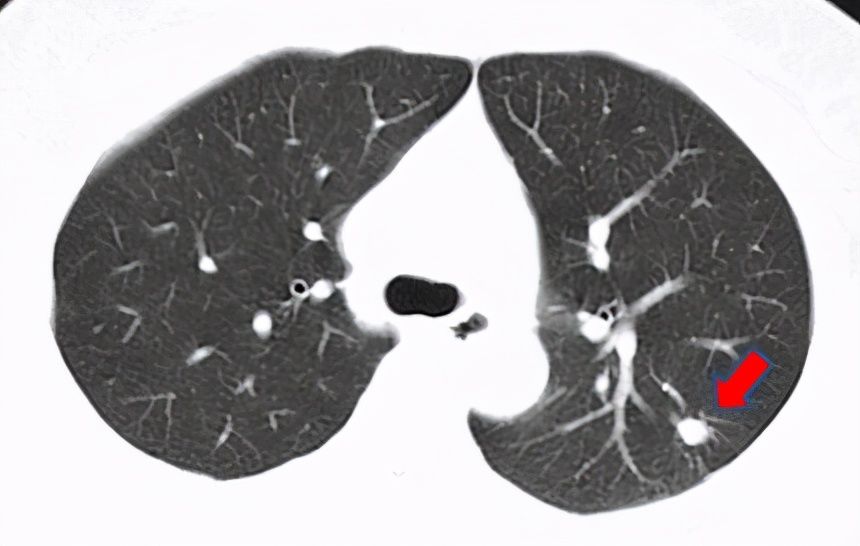

非结核分枝杆菌赵阿姨是一名普通的家庭妇女,年过半百,只求身体健康,能帮儿女带带孙辈。可是今年她莫名其妙开始咳嗽咳痰,一直不好,最近3个月还时不时发低烧。赵阿姨郁郁寡欢,儿女们急在心里,赶紧预约了医生。胸部CT吓人一跳:两肺有多发结节,赵阿姨乖乖吃了半个月的左氧氟沙星之后复查,没想到结节不仅没消失,反而逐渐增多了,一家人的心都悬了起来。